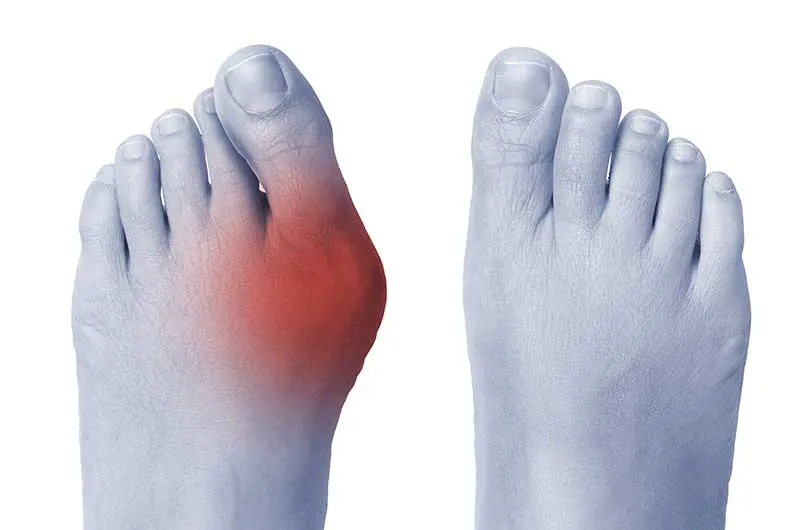

Haluks, czyli paluch koślawy (łac. hallux valgus), to znacznie więcej niż tylko defekt kosmetyczny. To postępująca deformacja stopy, która polega na odchyleniu palucha w kierunku pozostałych palców, jednocześnie powodując wysunięcie głowy pierwszej kości śródstopia na zewnątrz. Z czasem, jeśli problem jest ignorowany, może prowadzić do poważnych dolegliwości bólowych, stanów zapalnych, a nawet zmian zwyrodnieniowych w stawie. Co istotne, u dorosłych metody zachowawcze nie są w stanie cofnąć już istniejących zmian kostnych, dlatego tak ważne jest, aby nie bagatelizować pierwszych objawów.

- Zaczerwienienie i obrzęk wokół stawu, świadczące o toczącym się stanie zapalnym.

Postępująca deformacja stopy, widoczna gołym okiem, to kolejne ważne wskazanie. Jeśli zauważasz, że paluch coraz bardziej nachodzi na drugi palec, a przodostopie staje się coraz szersze, to sygnał, że problem się pogłębia. Trudności w dopasowaniu obuwia, o których już wspominałem, są bezpośrednią konsekwencją tych zmian. Dodatkowo, pojawiające się bolesne modzele, nagniotki czy otarcia na skórze, wynikające z nieprawidłowego ułożenia palców, również świadczą o konieczności interwencji.

Przewlekły stan zapalny i ryzyko powikłań: dlaczego nie warto dłużej czekać?

Przewlekły stan zapalny i obrzęk w okolicy stawu śródstopno-paliczkowego są nie tylko bolesne, ale mogą prowadzić do poważniejszych konsekwencji. Długotrwałe ignorowanie haluksa zwiększa ryzyko powikłań, takich jak uszkodzenia innych stawów stopy (np. metatarsalgia), nerwobóle, a nawet zmiany zwyrodnieniowe. Odkładanie zabiegu może sprawić, że deformacja stanie się trudniejsza do skorygowania, a proces rekonwalescencji będzie dłuższy i bardziej skomplikowany. Dlatego tak ważne jest, aby nie czekać, aż problem stanie się naprawdę poważny.